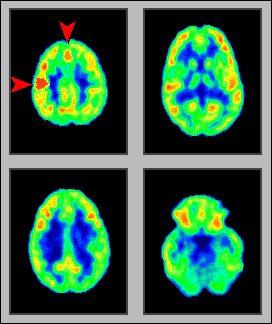

A good example of the fantastic

imaging capabilities of PET is shown in the images at the left, made by Dr. Marcus

Raichle, at the Neuroimaging Lab or

the Washington University School of Medicine, St Louis, USA.

These scans "were taken

under two different conditions. In the first one (uppermost image), an

individual was hearing a text, in order to learn a new language task. The color

map shows the regions of the brain which were activated by this task, in other

words, where there were cells working more than in their resting state, with a

higher metabolism (using more energy and more blood flow). The PET machine shows

the degree of activity in several tones of color, like in a rainbow. Yellow and

red regions are "hotter", that is, they indicate a higher cell

activity. Blue and black regions show decreased activity or none at all. While

obtaining this image, the patient was still unpracticed at the language learning

task. The highest brain activities are shown in an area called temporal lobe,

responsible for the hearing perception, and in another area called prefrontal

cortex, responsible for understanding language.

In the second condition

(lowermost image), the same individual has now learned the language task and is

spelling out. You can easily see in the color map that two different regions of

the brain were activated in each condition. Now the activity is concentrated in

the area of the cortex which is responsible for the motor control of voice, the

so-called area of Broca, so named because it was discovered by a French

physician named Paul Broca, in the turn of the century. Thus, the functional map

obtained with PET closely corresponds with what we know about the brain's

functional neuroanatomy, discovered by other methods. The difference here is

that we can actually obtain a real-time image of brain function."